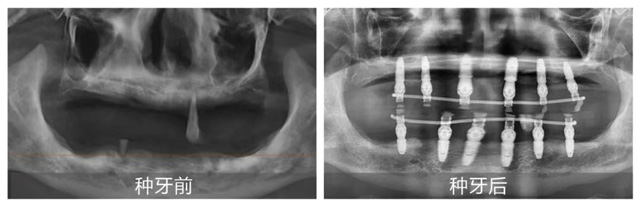

考慮到熊叔叔年齡較大且患有高血壓,全口種植風(fēng)險(xiǎn)大、術(shù)后反應(yīng)強(qiáng),張潔為其制定半口種植方案。手術(shù)在家人陪伴下順利結(jié)束,熊叔叔當(dāng)天就戴上臨時(shí)牙冠,恢復(fù)基礎(chǔ)飲食功能。他激動(dòng)地道,“這次終于種上了,原來(lái)種牙這么舒適,我根本不用操心,醫(yī)護(hù)人員領(lǐng)著我檢查,醫(yī)生做手術(shù)我都沒什么感覺。想到晚上就能吃東西,我太激動(dòng)了。”